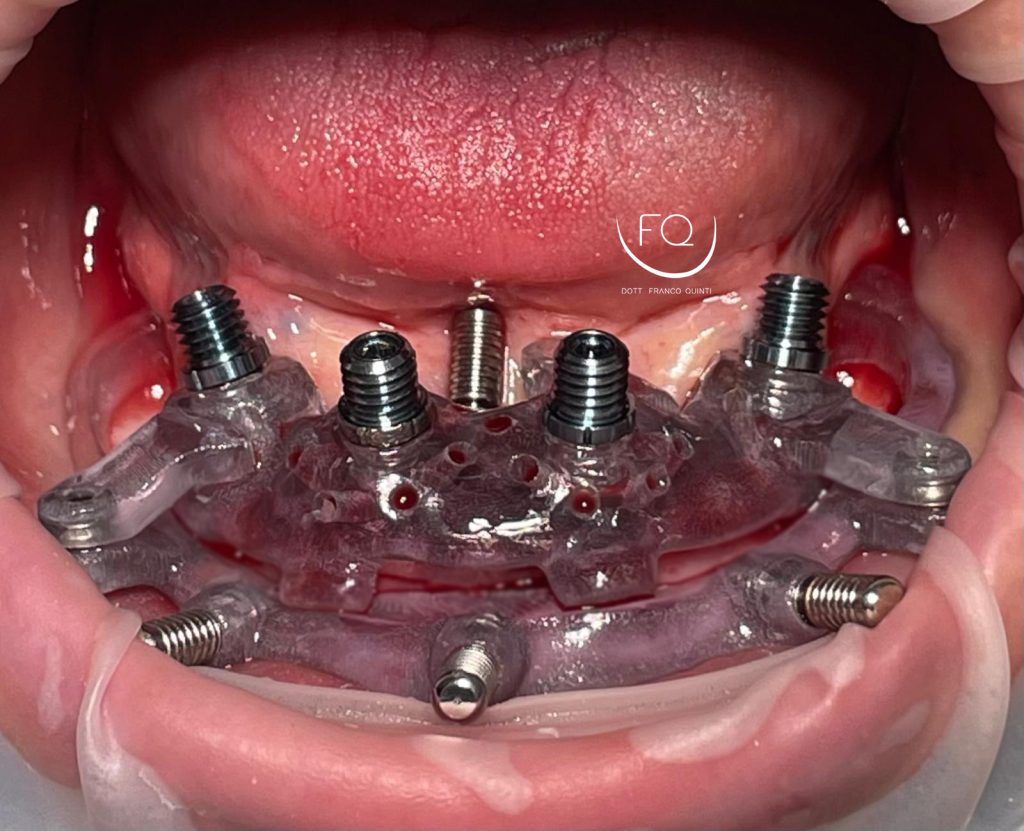

Oggi vi presento un caso di riabilitazione dell’arcata inferiore eseguito con l’utilizzo di dime scomponibili.

Il trattamento ha previsto l’inserimento di 4 impianti Prama Power di Sweden & Martina e la contestuale riabilitazione protesica provvisoria. Tra 3 mesi il caso verrà finalizzato con una protesi definitiva.